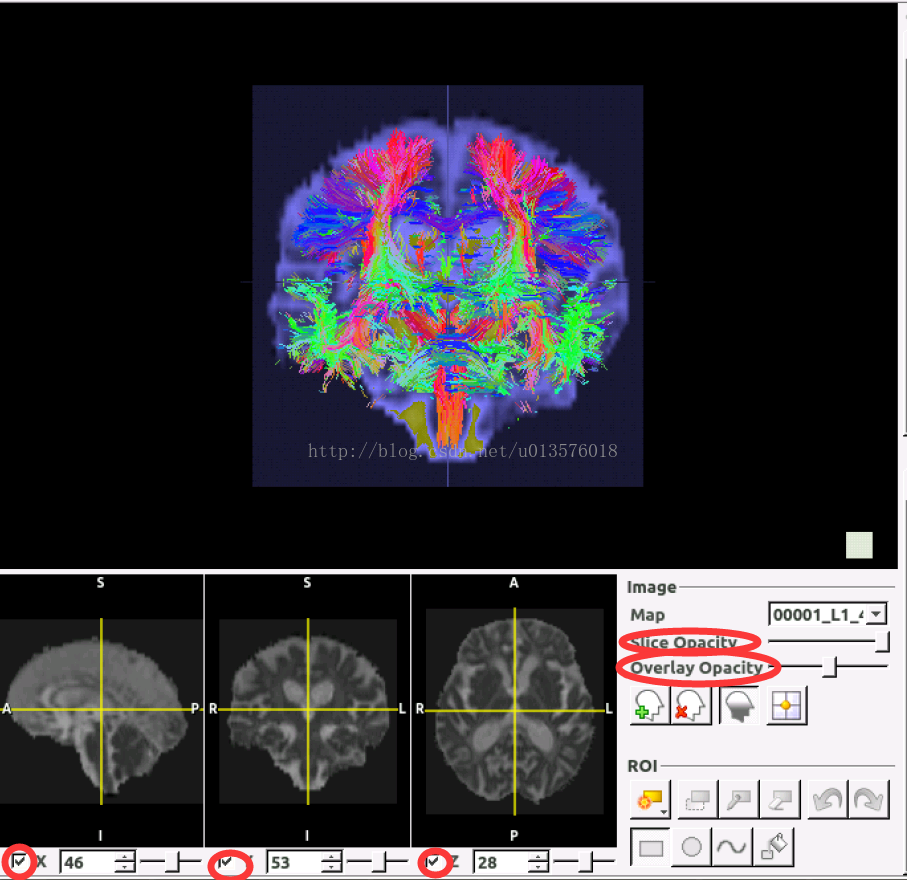

二、加载三维图像(以FA图像为例)

单击这个button,就可以打开一幅Image加载到Tracking的结果上。

这里我们加载一幅FA图像上去观察效果:

可以很明显的看到,当选择的FA维度与tracking结果的维度没有差异的时候,两者可以很好的overlay.

左下角的三个勾选框可以选择是否显示该断层的Image信息,同时可以对透明度进行设置。